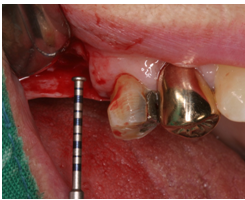

患者之後於96/11/08在右下第一小臼齒與植體間有膿胞產生,並於97/02/21確認右下第一小臼齒有根裂的情形,因此在97/02/29拔除此牙;經過將近半年後,於97/09/23放置一顆植體於此位置

97/02/21 確定根裂時拍的片子

97/02/21